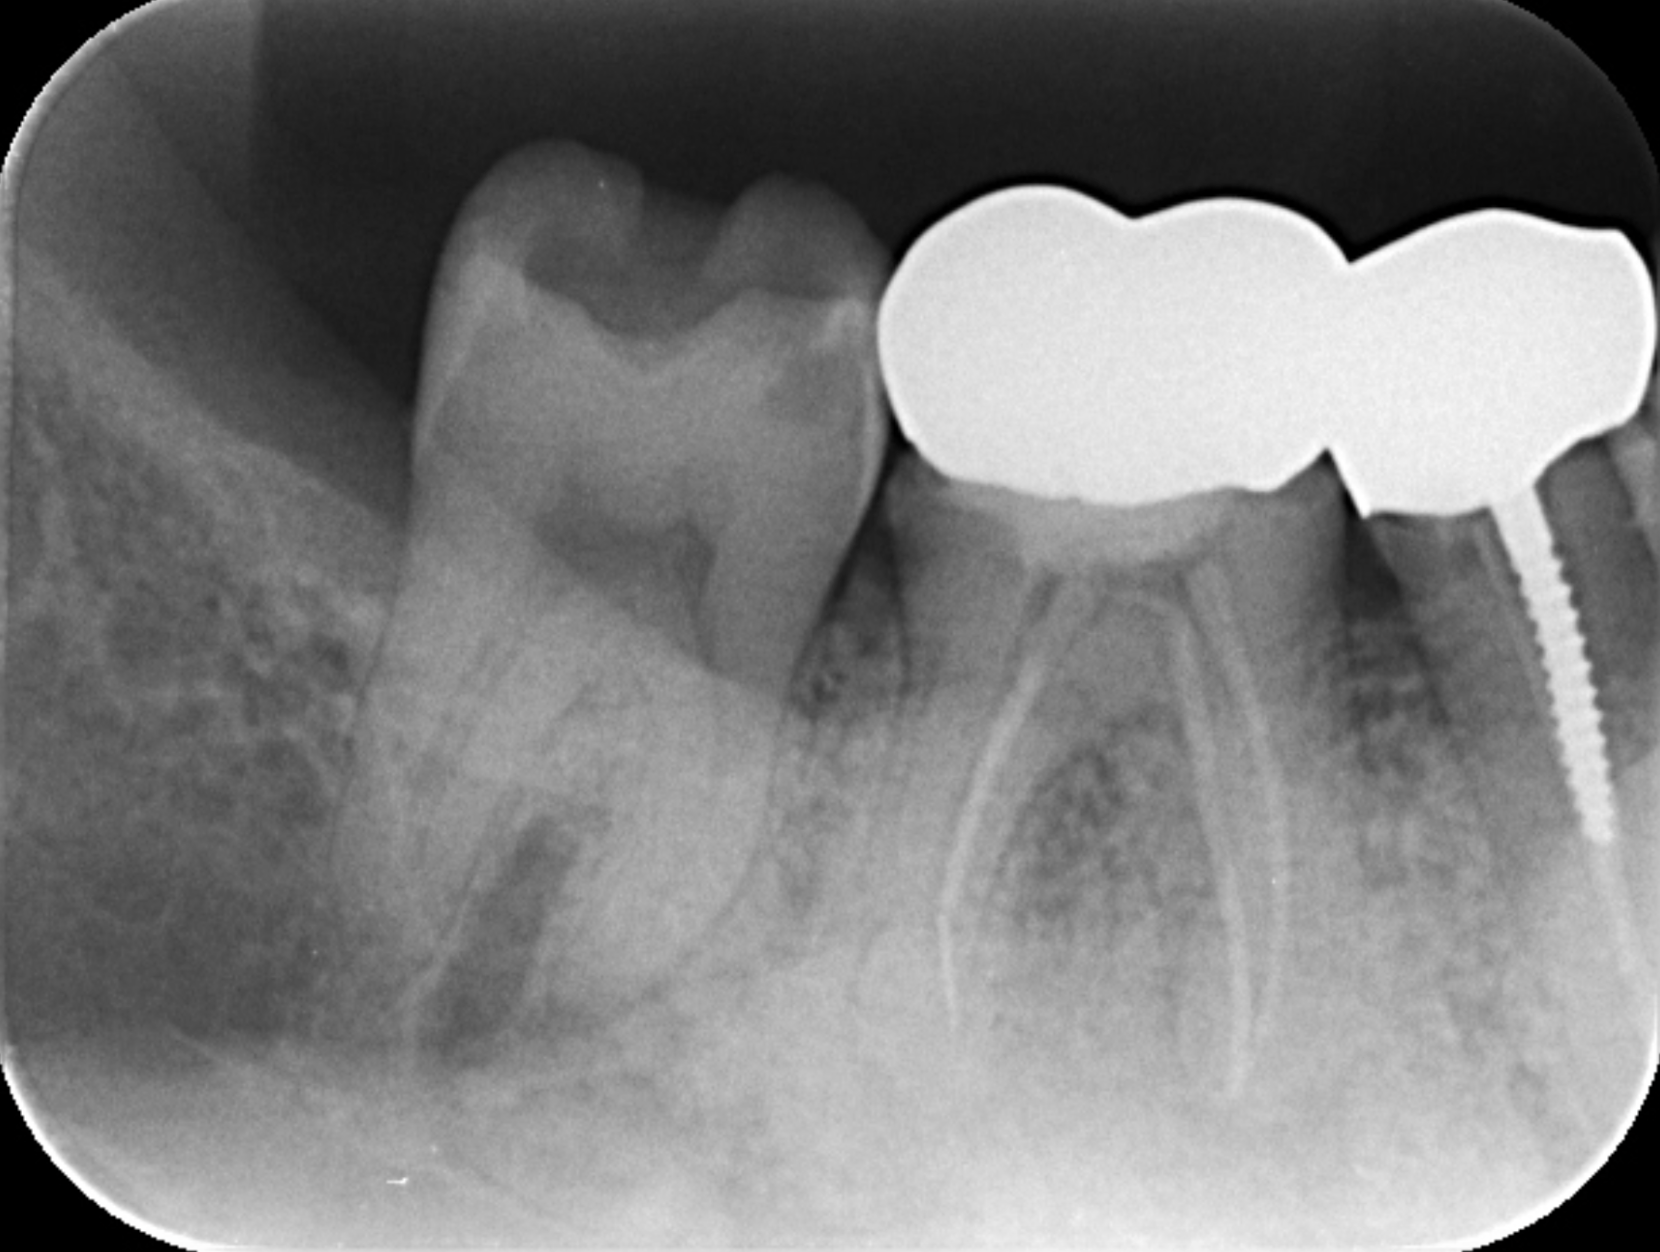

インプラントを用いたエクストリュージョン 2019.07.17インプラントの症例 費用:50万治療期間:8ヶ月リスク説明:下顎のインプラントは神経に近い恐れがあります。治療前保険の被せ物の中は虫歯だらけでした・・・歯を引き出す処置自分の歯を残したいと強く希望されたので、インプラント... 続きを読む